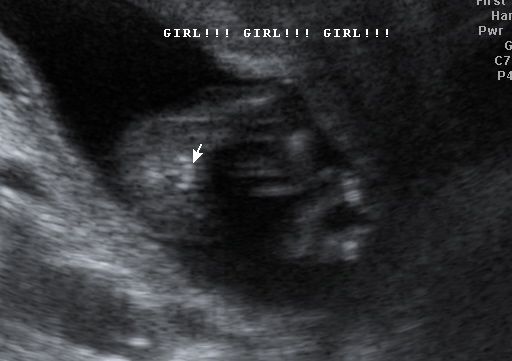

So tech was convinced this is a girl... do you think there is any doubt?? Please let me know if you think there is anyway it could be a boy!! I really think this is my girl:)